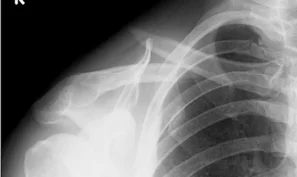

Clavicle Fracture

- Sites:

- Lateral thirds,

- Middle thirds, common (why?)

- Medial thirds

Its weakest point. The lateral fragment is depressed by the weight of the arm against trapezius, thus the shoulder droops, it is pulled medially forward by adductor function of pectoralis major causing the bone fragments to override.